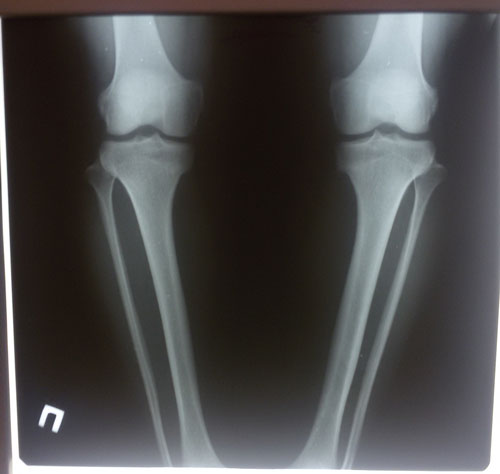

Диагноз: ахондроплазия, варусная деформация обеих голеней 155 градусов.

Исходник.